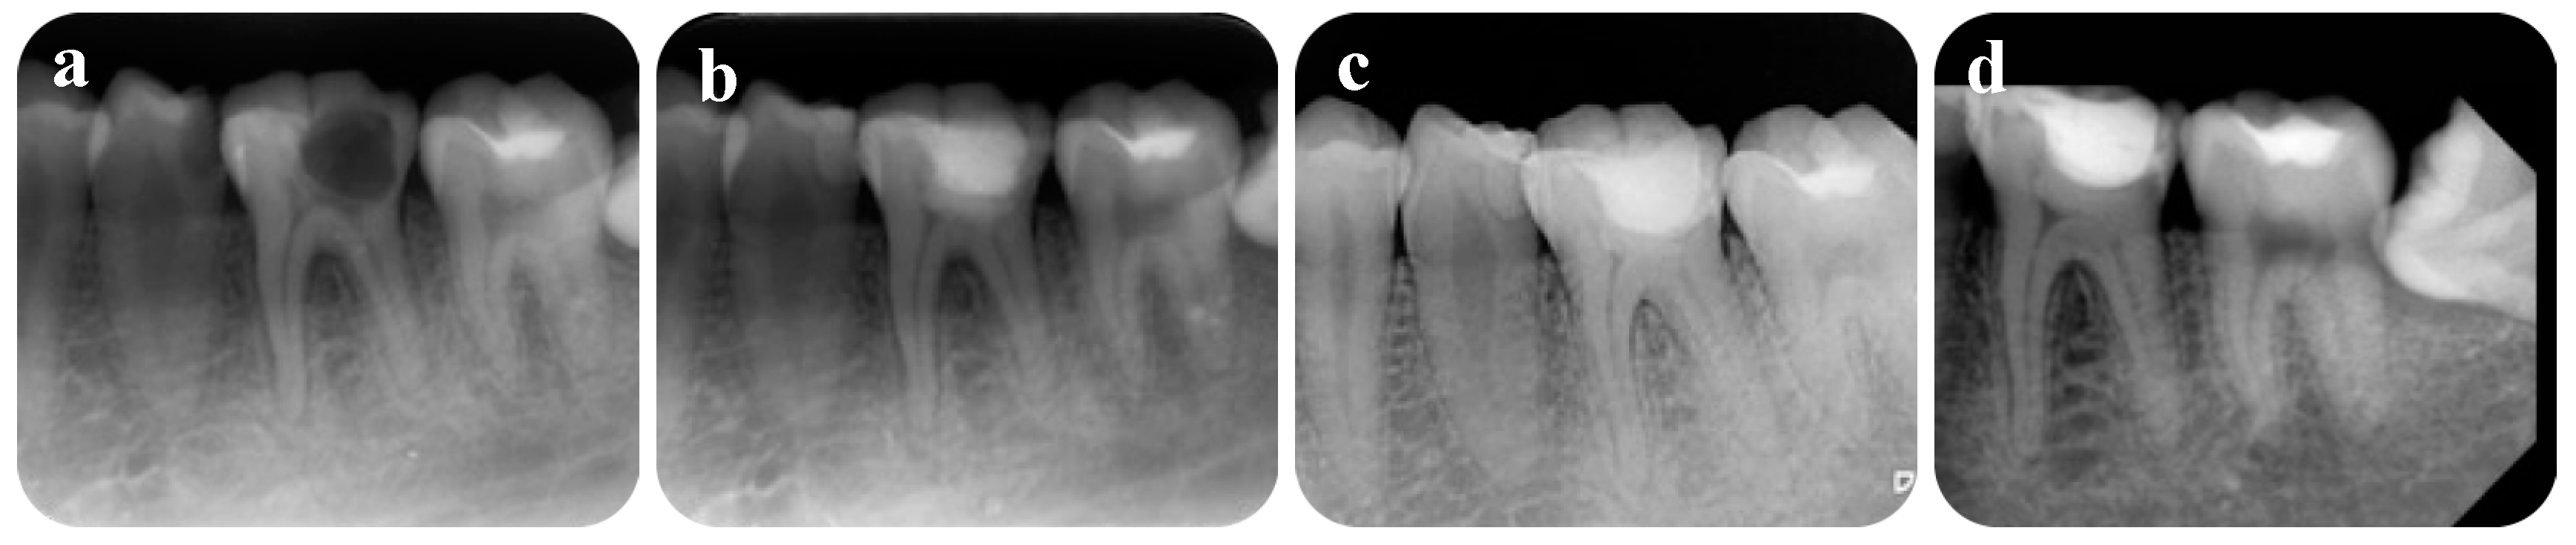

2. Case Presentation